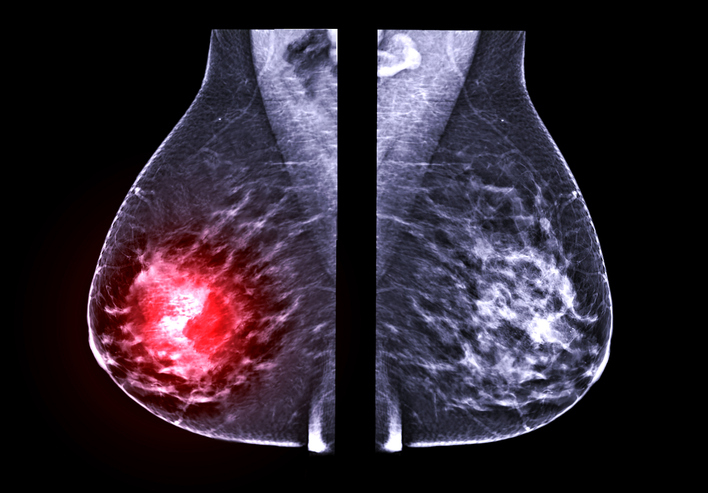

한국 여성이 폐경 이행기에 체질량 지수(BMI)에 따라 호르몬 변화와 유방 밀도가 달라지는데, 이게 유방암 발생 위험에 영향을 미칠 수 있다는 연구 결과가 발표됐다.

한국·일본 등 아시아 여성은 서구 여성보다 젊은 연령인 40대 후반에 유방암 발생이 정점을 보인다. 유방암은 여성호르몬에 영향을 받고, 유방 밀도가 높을수록 유방암이 생길 가능성이 커지는 것으로 알려졌다.

그 결과, 저체중 여성에서는 폐경 이행기 초기에 여성호르몬과 유방조직 밀도가 일시적으로 상승했다. 반면 비만 여성은 여성호르몬이 감소하고 유방 밀도도 낮아지는 경향을 보였다. 즉 이러한 변화는 폐경 이행기 초기에 저체중 여성에서 유방암 위험을 높일 수 있다는 것을 시사한다.